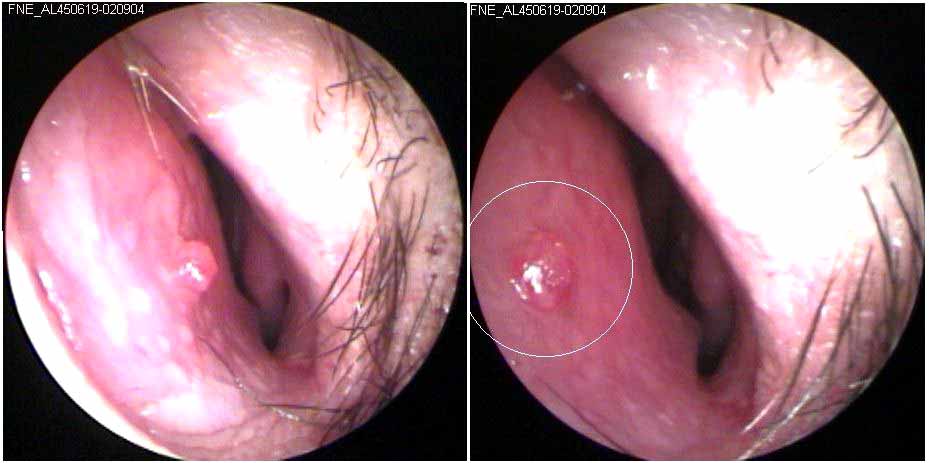

JFC Parálisis de C6 durante la inspiración

JFC Parálisis de C6 durante la fonación